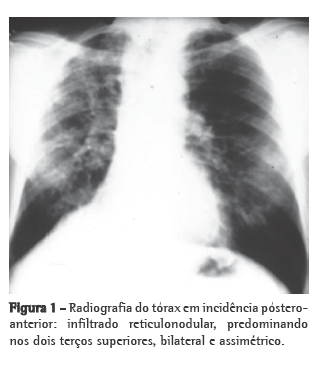

Aspectos radiográficosNa radiografia simples de tórax (Figura 1), pode ser visualizado infiltrado reticulonodular, predominante nos dois terços superiores de ambos os pulmões, assimétrico, com hipertransparência junto às bases pulmonares.(1,2,4)